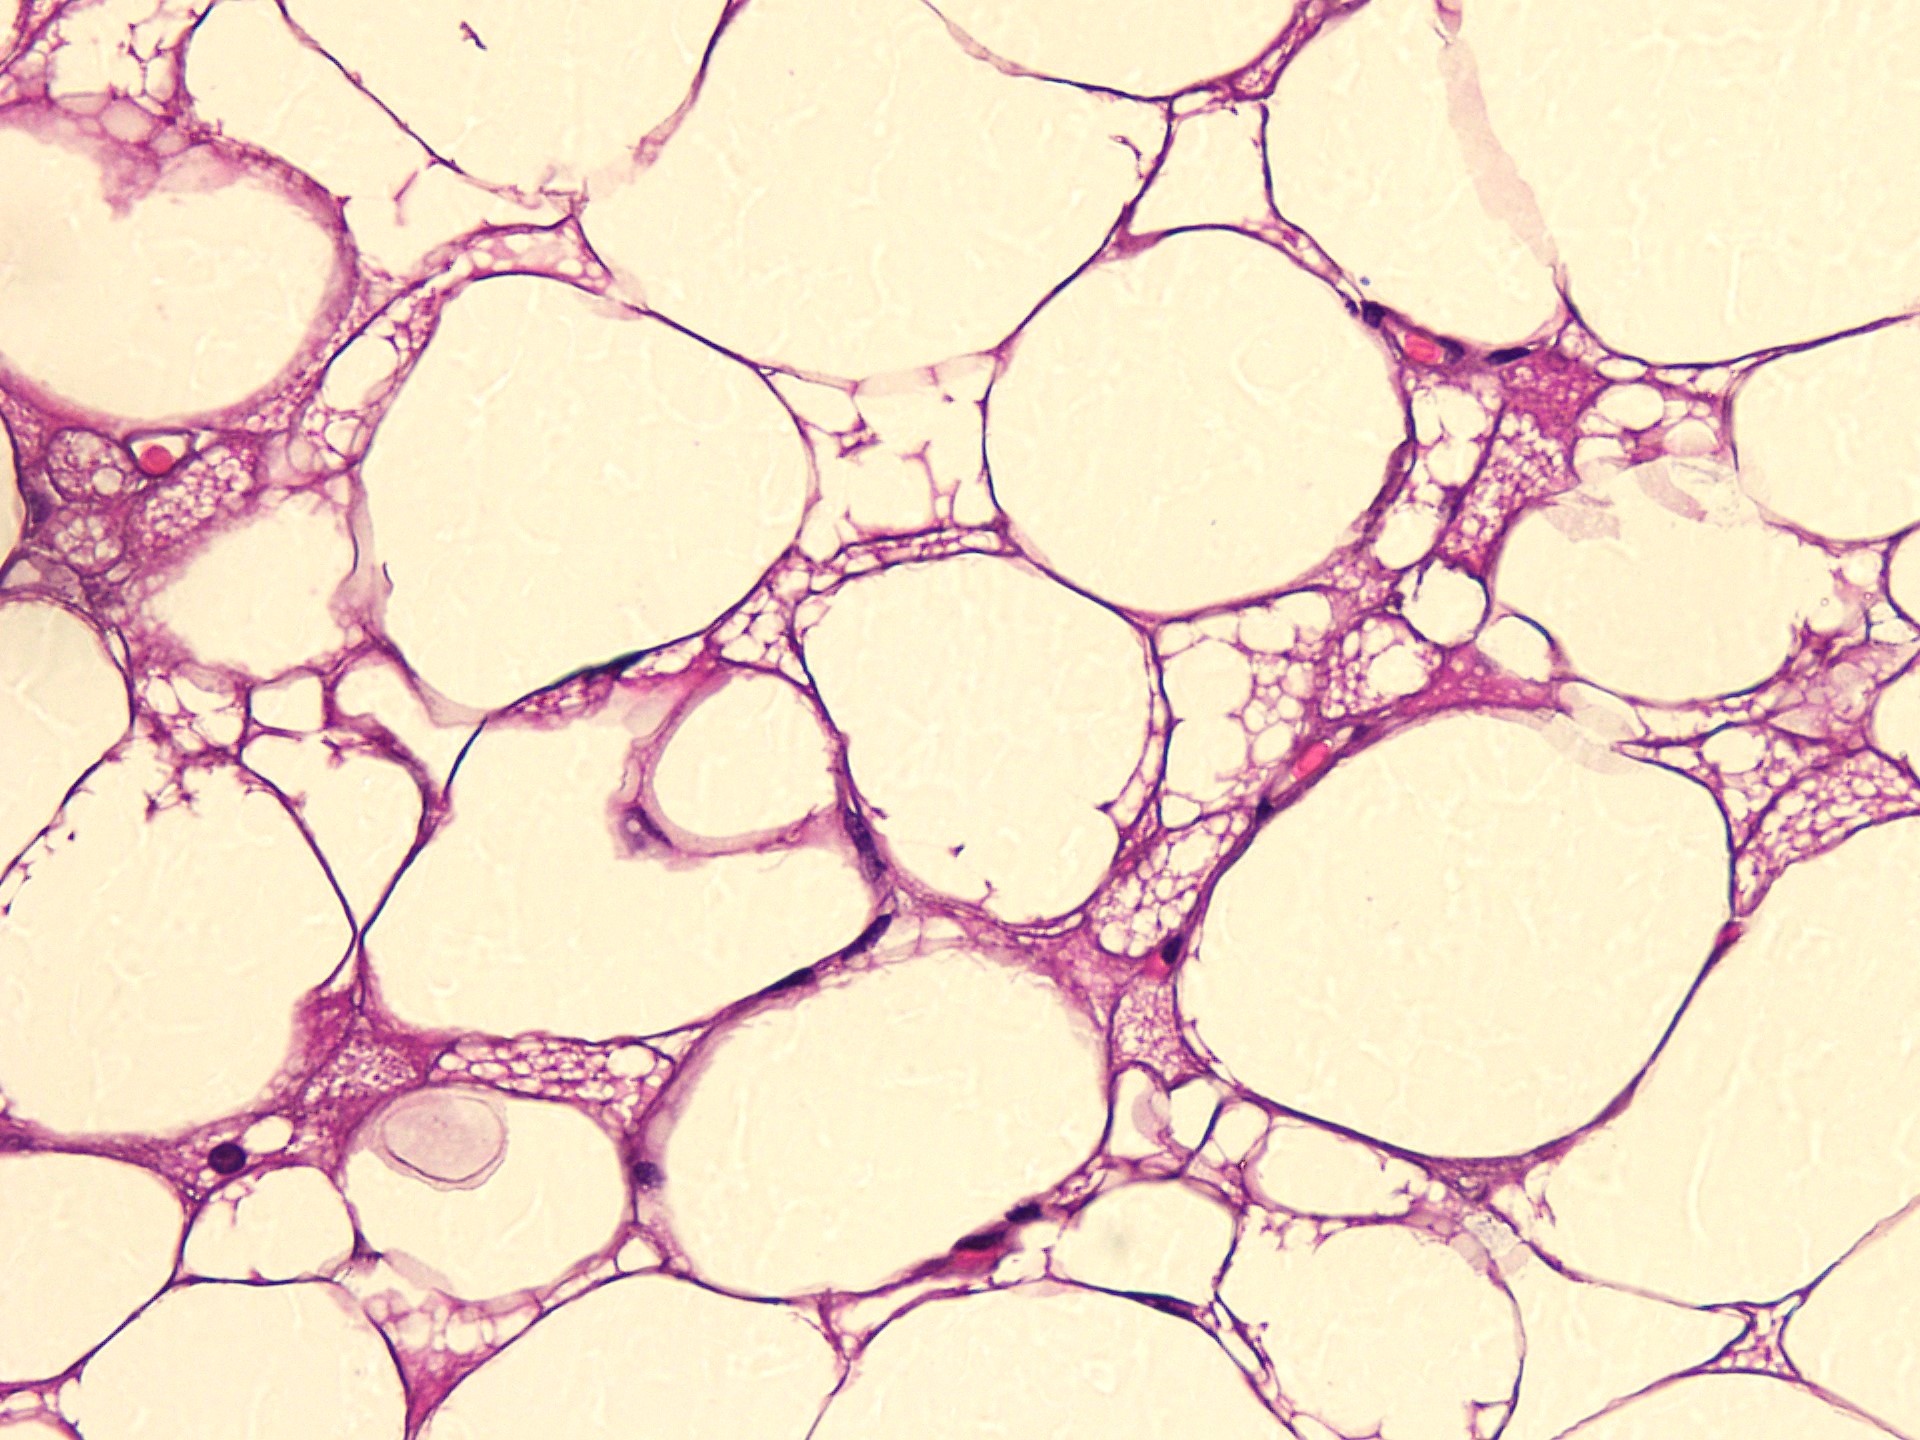

Microscopic (histologic) description

- Neoplastic lesion composed of polygonal brown fat cells with stromal cells in the background (Case Rep Oncol 2017;10:438)

- Large number of pale and eosinophilic brown fat cells with multivacuolated, eosinophilic granular cytoplasm and small central nucleus (about 70%) admixed with variable amount of univacuolated white cells (Case Rep Oncol 2017;10:438, Am J Case Rep 2020;21:e921447, J Comput Assist Tomogr 2019;43:793, J Pathol Transl Med 2017;51:499, Am J Surg Pathol 2018;42:951, Virchows Arch 2021;478:527)

- Multivacuolations resemble lipoblasts

- Morphological variations or subtypes: typical, myxoid (9%), lipoma-like (7%), spindle cell (2%), thick bundles of collagen fibers, presence of mast cells and exclusively containing brown fat cells (Case Rep Oncol 2017;10:438, Am J Case Rep 2020;21:e921447, Virchows Arch 2021;478:527)

- Cytological atypia, necrosis and mitosis is unusual (J Pathol Transl Med 2017;51:499, Am J Surg Pathol 2018;42:951, BMC Surg 2021;21:30)

Microscopic (histologic) images